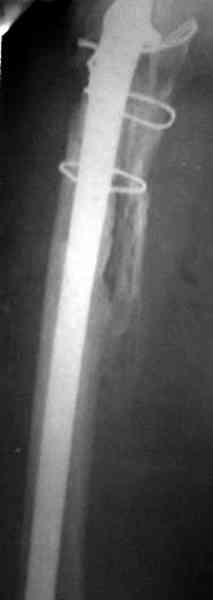

Приглашенный хирург установил ревизионный вариант бедренного компонента без замены ацетабулярного компонента, что осложнилось нагноением и свищами на уровне сустава и средней трети бедра. После двухгодичного безуспешного лечения перевязками и антибиотиками больная обратилась к нам на консультацию.

Повторная операция по удалению тотального протеза с irrigation&debridment, канал после очистки цемента обильно промыт и рассверлен римером.

Для спейсера в бедро использовал старый длинный бедренний компонент меньшего диаметра, облепленный со всех сторон цементом с антибиотиком.

№3-6 снимки с осложнением